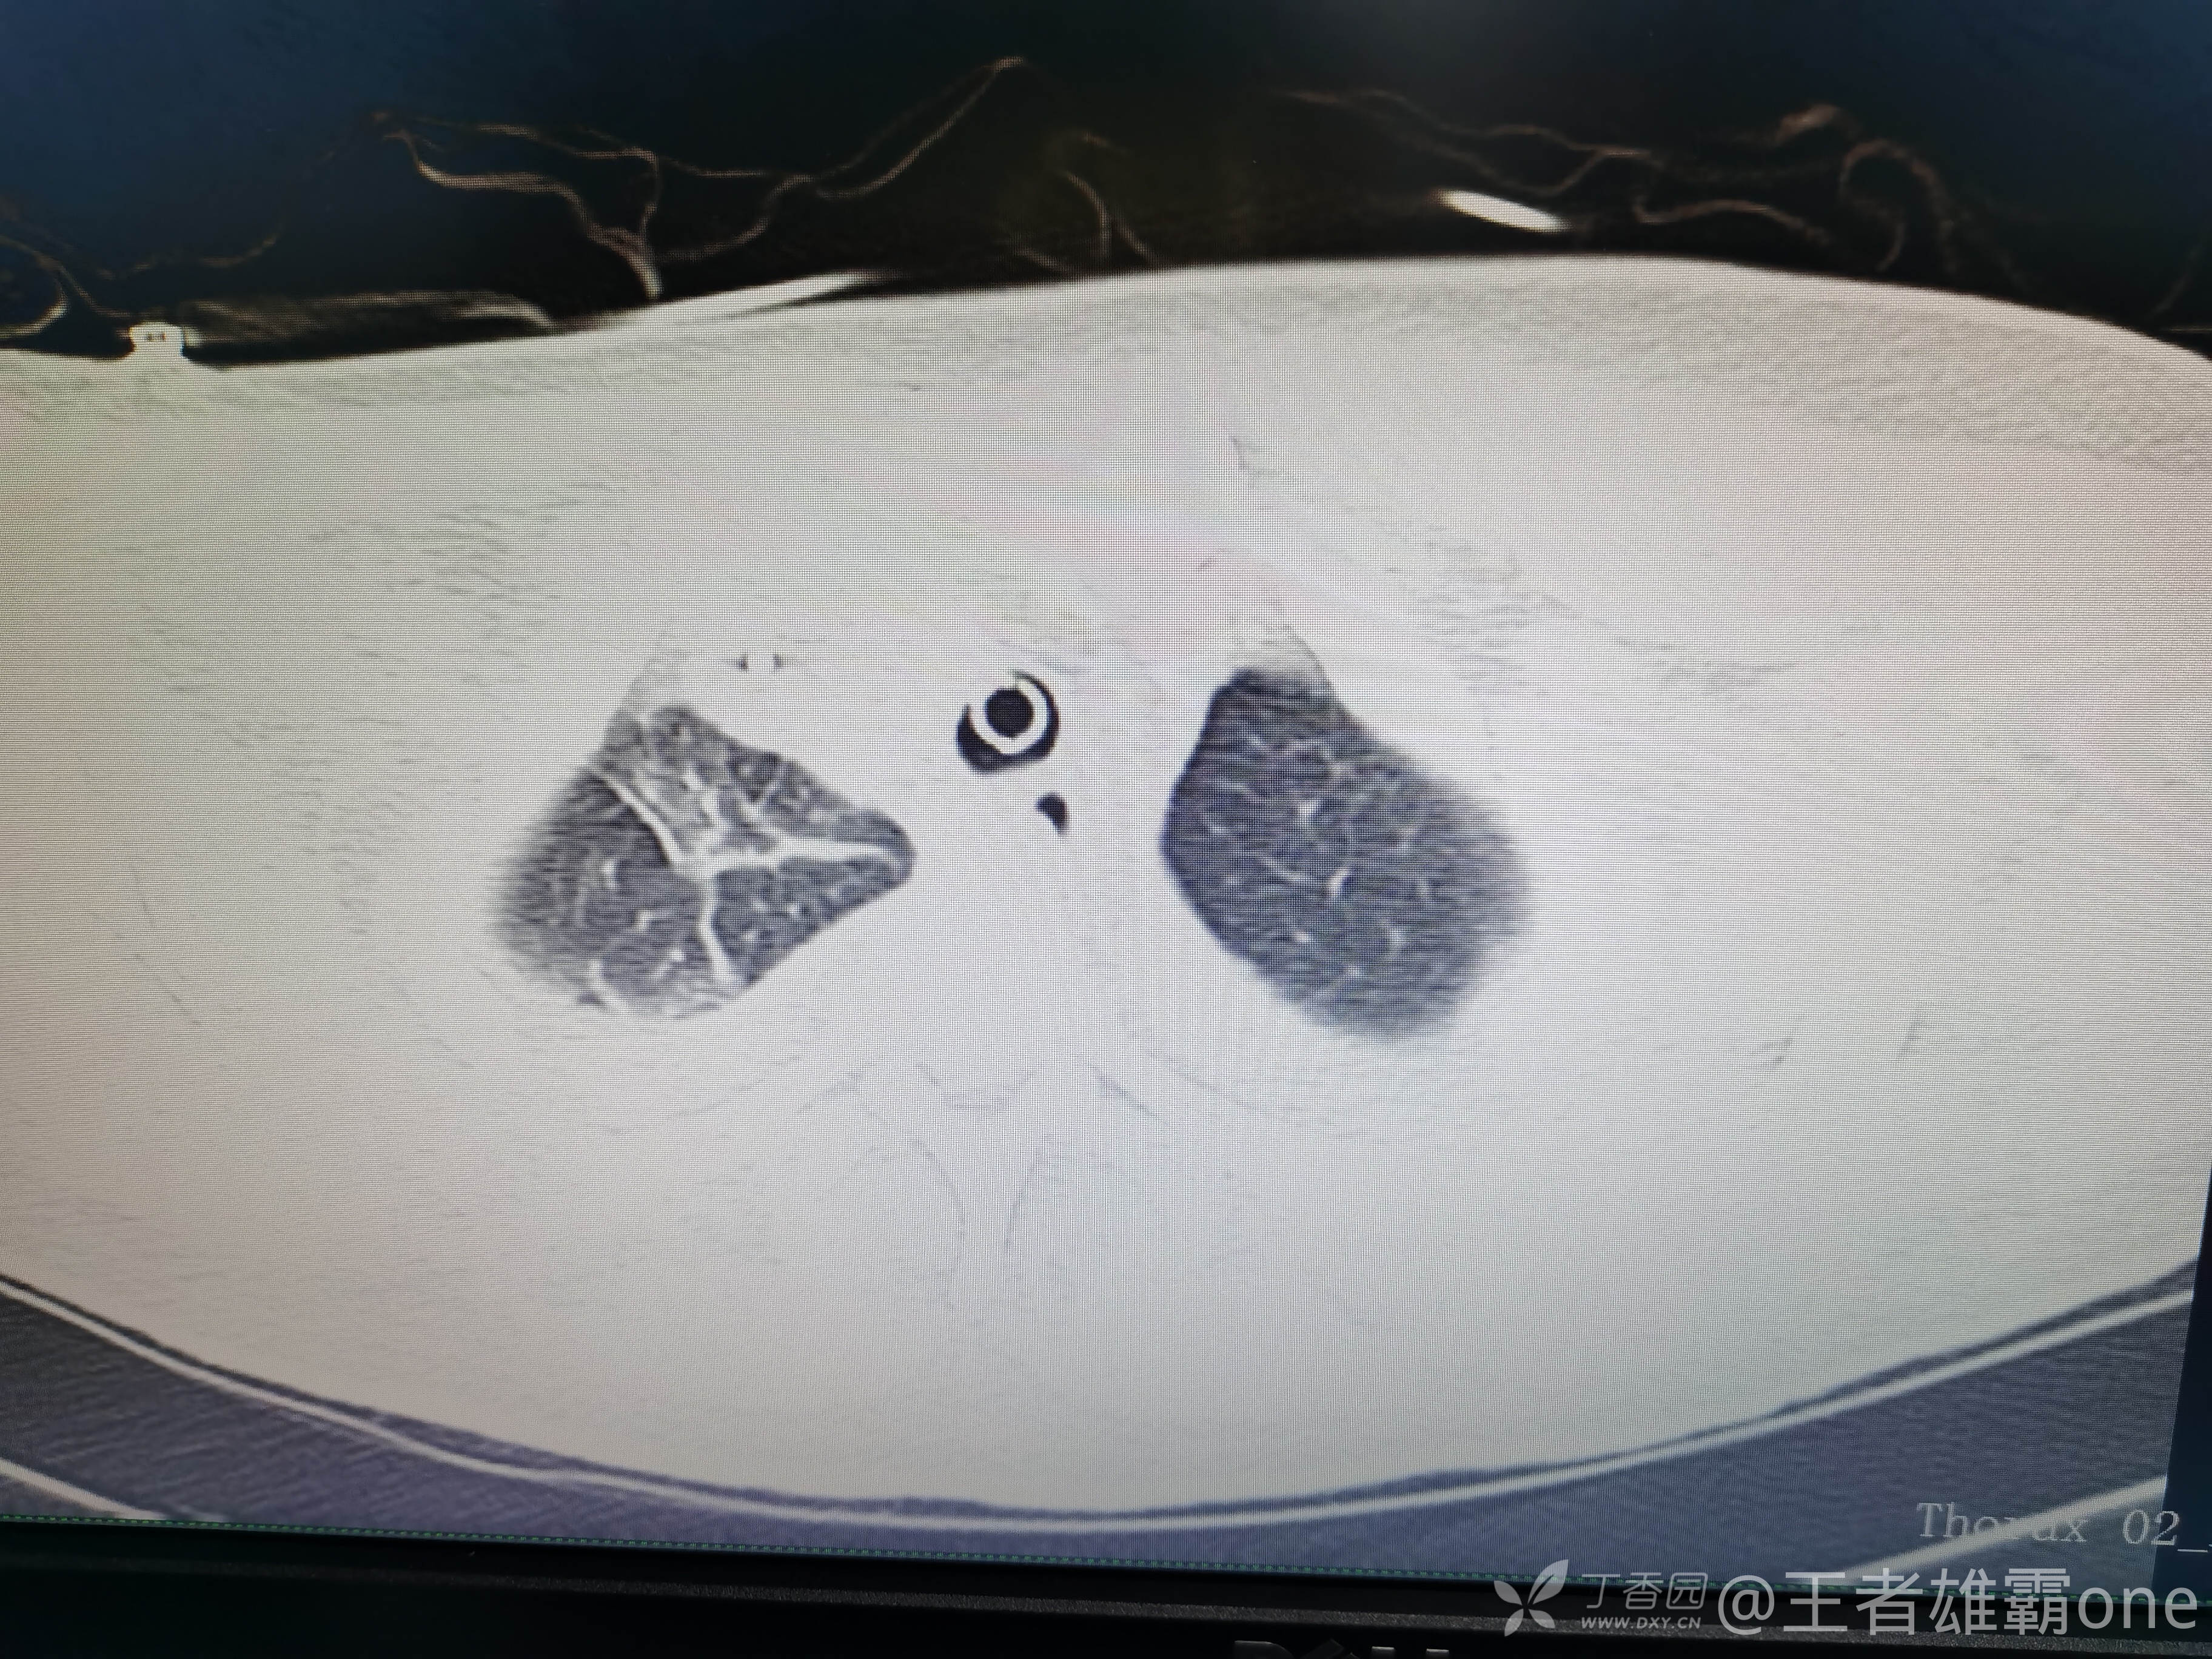

早上复查血常规:血红蛋白100g/L,白细胞11.1×109/L,血小板29×109/L。凝血功能:APTT37.9s,纤维蛋白原3.01g/L,凝血酶时间18.6s,D二聚体21530ug/L。生化:白蛋白36.2g/L,胆红素指标正常,谷丙56U/L,总胆红素38mmol/L,直接胆红素12.1mmol/L,谷草57U/L,肌酐91.1ummol/L,尿素13.97mmol/L,超敏C反应蛋白142.1mg/L。降钙素原17.70ng/ml。脑钠肽前体2164pg/ml。复查胸部CT:

那么问题来了,出现呼吸衰竭气管插管的病因是?请大家讨论分析!